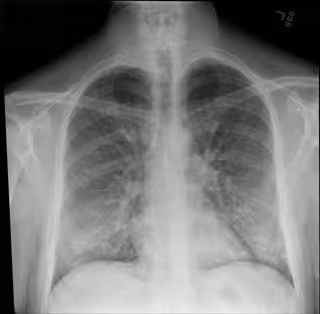

Las radiografías de tórax realizadas en adultos jóvenes y de mediana edad con covid-19 cuando llegan a urgencias pueden ayudar a los médicos a predecir quién tiene un mayor riesgo de enfermedad grave e intubación, informan los investigadores del Mount Sinai en el primer estudio de este tipo, que publica la revista 'Radiology'.

La investigación identifica qué pacientes pueden necesitar ser hospitalizados e intubados en función de la gravedad de los patrones de coronavirus en los pulmones observados en las radiografías, utilizando un sistema de puntuación único para evaluar la gravedad Los resultados podrían ayudar a los médicos a identificar, clasificar y tratar a estos pacientes de alto riesgo más rápidamente.

Los investigadores se centraron en la radiografía de tórax de cada paciente para examinar los patrones de coronavirus en sus pulmones, observando las opacidades (marcas circulares blancas asociadas con COVID) y dónde estaban esos patrones.

Dividieron los rayos X en seis zonas (superior derecha, superior izquierda, media derecha, media izquierda, inferior derecha e inferior izquierda) y desarrollaron un sistema de puntuación de cero a seis para cuantificar la gravedad. La puntuación total dependía de cuántas zonas aparecían enfermedades. La puntuación de gravedad más baja variaba de cero a dos, y la más alta, de tres a seis.

De los 338 pacientes, 145 fueron ingresados. Los pacientes con puntuaciones más altas de radiografías de tórax tenían 6,2 veces más probabilidades de requerir hospitalización y 4,7 veces más probabilidades de ser intubardos.